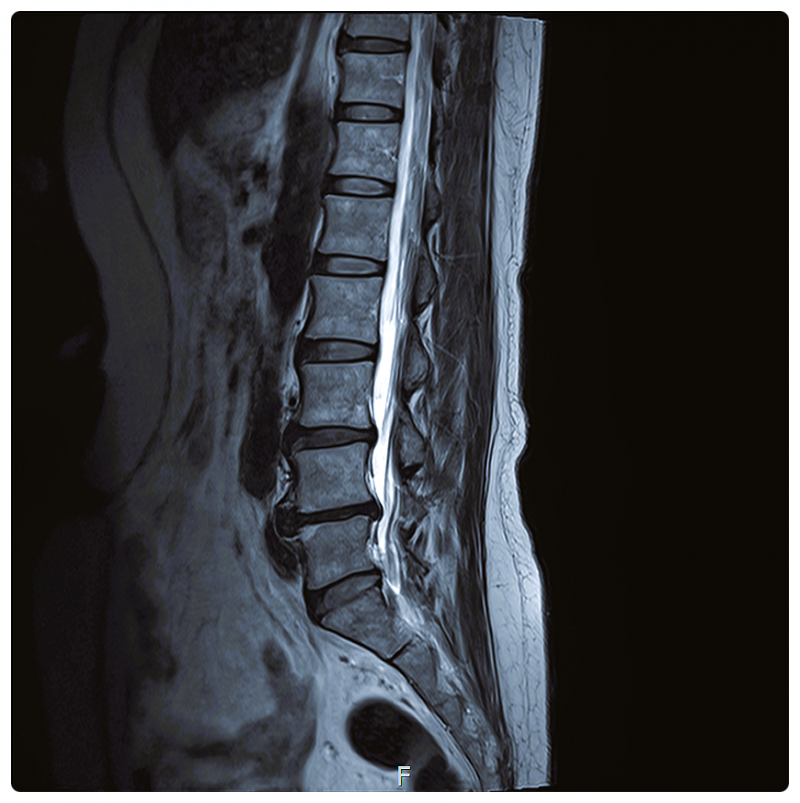

예를 들어 디스크가 돌출되어 신경을 압박했다면,

그 구조적인 문제를 정리하는 데에는 분명 큰 역할을 하게 됩니다.

대부분의 척추·관절 문제는 어느 날 갑자기 생기지 않습니다.

잘못된 자세, 반복된 동작,

특정 근육만 과도하게 사용하는 생활 습관이 쌓여 손상으로 이어지는 경우가 많습니다.